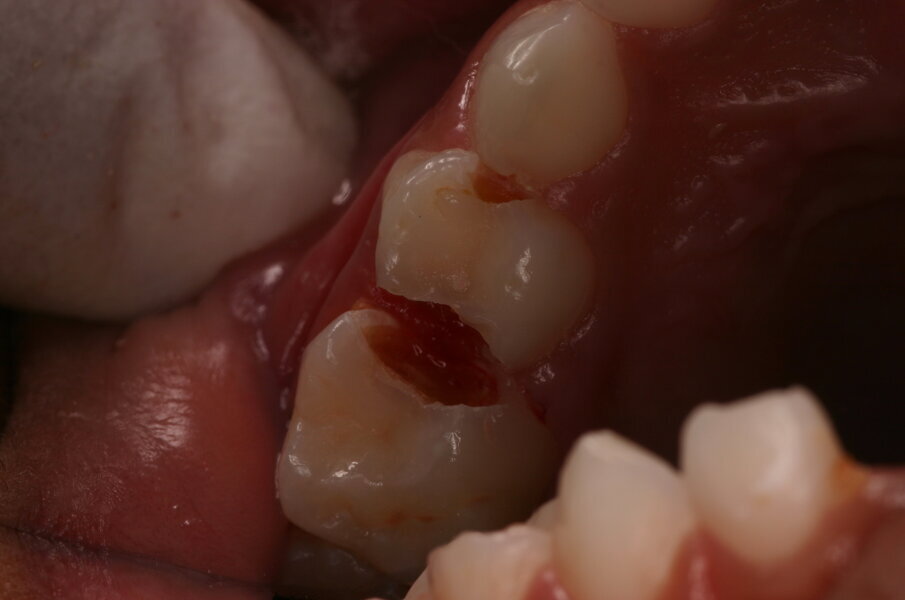

Tandenpoetsen doen veel mensen, ook al verschilt de mate van grondigheid ervan. Weinig suiker gebruiken is veel lastiger. Immers mensen moeten iets lekkers achterwege laten en dat is moeilijk. Het is belangrijk om goede hoofdmaaltijden te gebruiken om niet te hoeven snoepen voor energie. Wil je dit bereiken dan is verwijzing naar een diëtist misschien wel de geëigende weg. Daarom is het altijd belangrijk om het grondig reinigen van tandoppervlakken te benadrukken in het voorkomen van tandcariës. In veel gevallen lukt het ouders en kind(eren) om tanden en kiezen gaaf te houden. Bij anderen is dat moeilijker. Dentinecaviteiten ontstaan en de aanjager ervan moet beteugeld worden. Die aanjager is cariogene plaque. In een caviteit is die plaque op de bodem en aan de wanden te vinden. Om dezelfde reden als voor het gezond houden van gave tandoppervlakken moet plaque uit de caviteit verwijderd worden. De meest voor de hand liggende manier om dat te bereiken is door het schoonpoetsen met tandenborstel en fluoridehoudende tandpasta. Echter, de caviteit moet dan wel toegankelijk zijn. Het is duidelijk dat de toegankelijkheid in kleine caviteiten moeilijk tot onmogelijk is. Grote caviteiten kunnen gemakkelijk worden bereikt en middelgrote caviteiten kunnen vergroot worden. Dat laatste kan gebeuren met een diamantfineerboortje (afbeelding 1) of met een glazuurmes (afbeelding 2). Door het glazuurmes te plaatsen op onondersteund glazuur fractureert dit glazuur onder geringe druk en wordt voldoende toegang gecreëerd (afbeelding 3a-b). Deze poetsbehandeling van cariës wordt causale behandeling genoemd.

Afbeelding 5a. Onvoldoende toegankelijke caviteit mesiaal in de 65, distaal in de 64 en mesiaal in de 64.

Afbeelding 5b. De gedemineraliseerde caviteitsranden zijn onondersteund en fractureren gemakkelijk door met een glazuurmes erop te drukken.

Afbeelding 5c. De kleine mesiale caviteit in de 64 is door middel van de ART-methode gerestaureerd. De andere twee caviteiten zijn nu toegankelijk voor tandenborstel en fluoridetandpasta.

Afbeelding 6. Resultaat van de UCT-behandeling na twee jaar. De mond en caviteiten zijn schoon en het ziekteproces is tot stilstand gekomen. De ART-restauraties zien er goed uit.

De causale behandeling van gecaviteerde dentinelaesies in de tijdelijke dentitie bestaat dus uit:

- Schoonpoetsen met tandenborstel en fluoridehoudende tandpasta van toegankelijke caviteiten (afbeelding 4).

- Toegankelijk maken van middelgrote niet-toegangelijke caviteiten, behandelen volgens 1.

Kleine caviteiten kunnen gerestaureerd worden volgens de atraumatic restorative treatment (ART) (afbeelding 5a-c).

Deze gecombineerde behandelaanpak (ART en caviteit schoonpoetsen) wordt de ultra-conservative treatment (UCT) genoemd en is onderzocht in Brazilië. Bij de kinderen in de controlegroepen werden alle dentinecaviteiten in tijdelijke gebitselementen gerestaureerd met amalgaam of door middel van de ART-methode behandeld. In de experimentele groep werden de kinderen dus behandeld met de UCT-methode. De klinische uitkomstmaat was het exfoliëren van de melkmolaren en -cuspidaten zonder pathologie. Andere uitkomstmaten waren: mate van angst en ongerief, mate van zelfzorg en mate van malocclusie in het blijvende gebit.